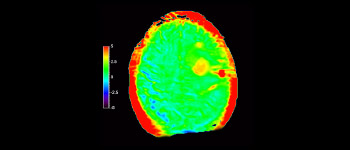

En una sociedad con una alta incidencia de trastornos neurológicos, Philips se compromete a ofrecer una excelente asistencia en el tratamiento y claridad en el diagnóstico para todos los pacientes. Hoy en día, aunque la RM es la modalidad de referencia para la adquisición de imágenes de neurooncología, su precisión a la hora de clasificar los tumores y de evaluar el seguimiento de los tratamientos aún tiene mucho margen de mejora. 3D APT (Amide Proton Transfer, transferencia de protones de amidas) es un exclusivo método de adquisición de imágenes por RM cerebral sin contraste que tiene por objetivo ofrecer un diagnóstico de neurooncología más fiable. 3D APT utiliza la presencia de proteínas celulares endógenas para producir una señal de RM que se corresponde directamente con la proliferación celular, que es un marcador de la actividad tumoral. 3D APT puede ayudar a los profesionales de la salud debidamente instruidos a diferenciar los gliomas de baja malignidad de los gliomas más graves, así como a diferenciar la progresión tumoral del efecto del tratamiento1.

Cerebro con glioblastoma

con 3D APT